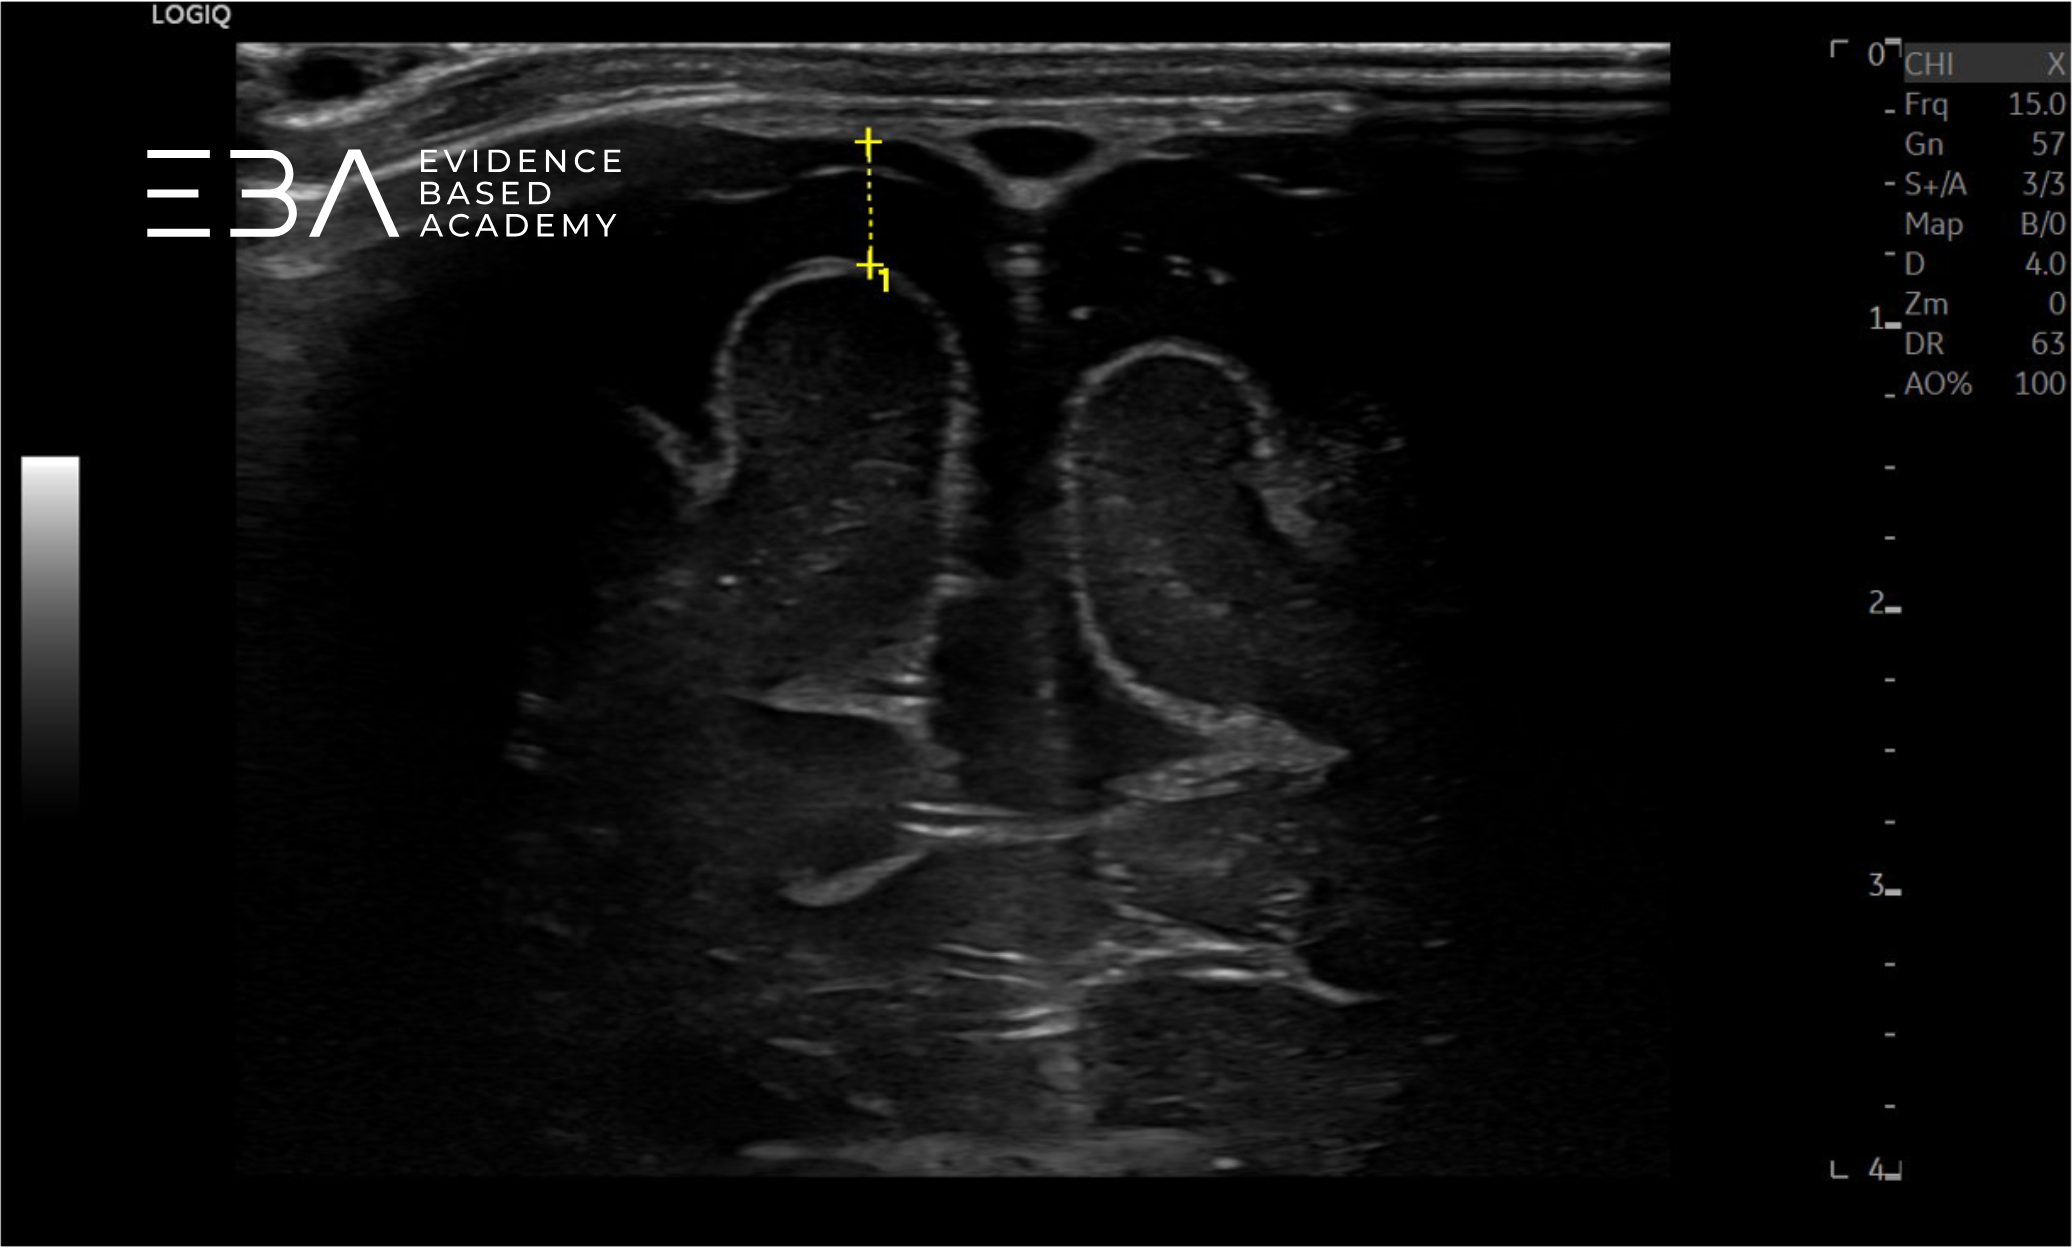

zdj. a

Głowica liniowa. Pomiar szerokości przestrzeni przymózgowej podpajęczynówkowej na sklepistości czaszki.